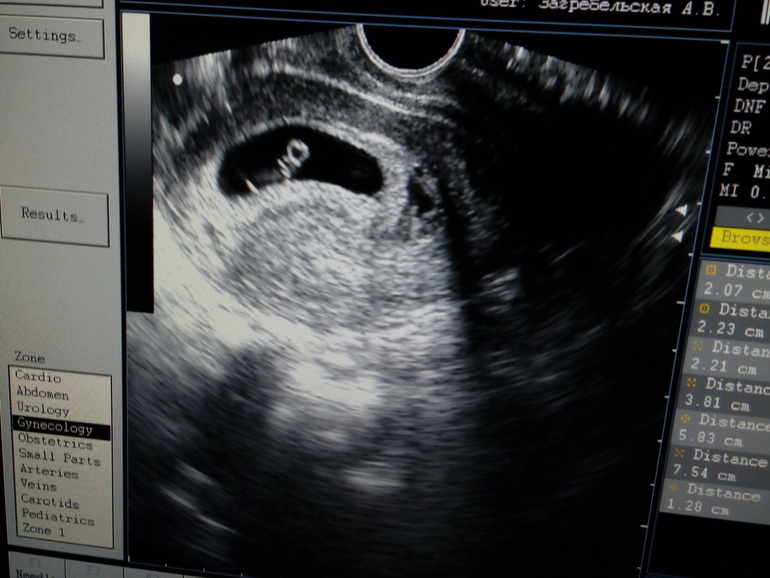

УЗИ 7+2н

ФолликулометрияСегодня было наше первое УЗИ. Все хорошо, Б маточная, развивается. Поставили по размеру эмбриончика срок 6-7 недель

Странно, но СВД не написали. ПЯ расположено по передней стенке

Только КТР 1,30 см, сердцебиение 148уд (мне не включали)

ЖТ в ПЯ 2,23х2,07 см

А вот и фото самой креветочки. Делали трансвагинально. Какие предположения по полу исходя из расположения?